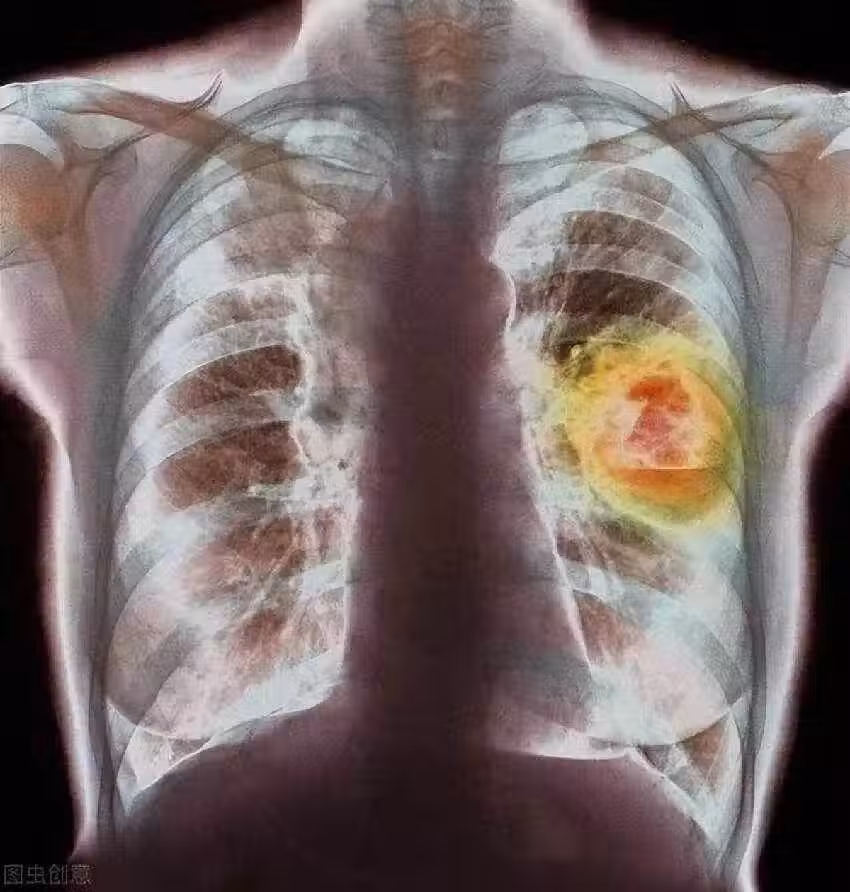

58歲婦女確診肺癌,強忍淚水坦言:手部早出現了問題,沒有多重視